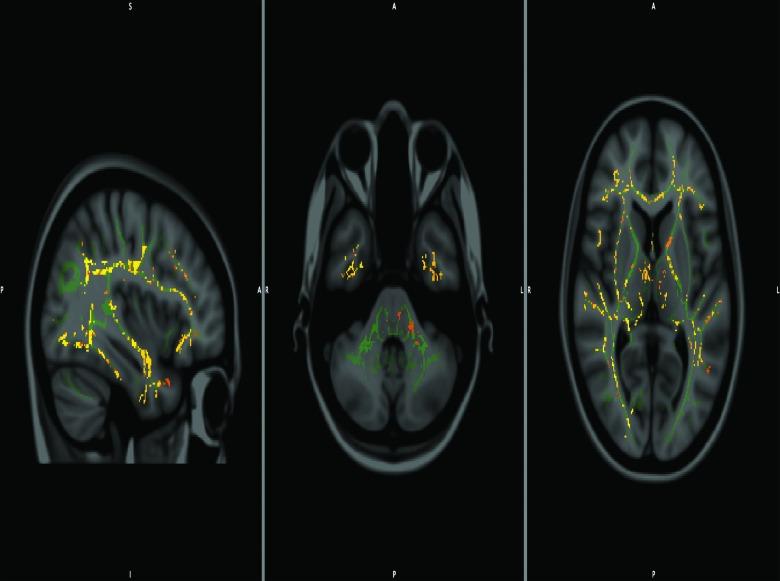

We explored the prognostic value of diffusion tensor imaging (DTI) parameters of selected white matter (WM) tracts in predicting neuropsychological outcome, both at baseline and 6 months later, among well-characterized patients diagnosed with mild traumatic brain injury (mTBI). Sixty-one patients with mTBI (mean age=27.08; standard deviation [SD], 8.55) underwent scanning at an average of 10 h (SD, 4.26) post-trauma along with assessment of their neuropsychological performance at an average of 4.35 h (SD, 7.08) upon full Glasgow Coma Scale recovery. Results were then compared to 19 healthy control participants (mean age=29.05; SD, 5.84), both in the acute stage and 6 months post-trauma. DTI and neuropsychological measures between acute and chronic phases were compared, and significant differences emerged. Specifically, chronic-phase fractional anisotropy and radial diffusivity values showed significant group differences in the corona radiata, anterior limb of internal capsule, cingulum, superior longitudinal fasciculus, optic radiation, and genu of corpus callosum. Findings also demonstrated associations between DTI indices and neuropsychological outcome across two time points. Our results provide new evidence for the use of DTI as an imaging biomarker and indicator of WM damage occurring in the context of mTBI, and they underscore the dynamic nature of brain injury and possible biological basis of chronic neurocognitive alterations.

我们探讨了在确诊为轻度创伤性脑损伤(mTBI)的特征明确的患者中,选定白质(WM)束的扩散张量成像(DTI)参数在预测神经心理学结果方面的预后价值,包括在基线时和6个月后。61例mTBI患者(平均年龄=27.08岁;标准差[SD],8.55)在创伤后平均10小时(SD,4.26)接受扫描,并在格拉斯哥昏迷量表完全恢复后平均4.35小时(SD,7.08)评估其神经心理学表现。然后将结果与19名健康对照参与者(平均年龄=29.05岁;SD,5.84)在急性期和创伤后6个月时进行比较。比较了急性期和慢性期之间的DTI和神经心理学测量结果,出现了显著差异。具体而言,慢性期的分数各向异性和径向扩散率值在放射冠、内囊前肢、扣带、上纵束、视辐射和胼胝体膝部显示出显著的组间差异。研究结果还表明,在两个时间点上,DTI指数与神经心理学结果之间存在关联。我们的结果为DTI作为mTBI背景下发生的WM损伤的成像生物标志物和指标提供了新证据,并强调了脑损伤的动态性质以及慢性神经认知改变的可能生物学基础。